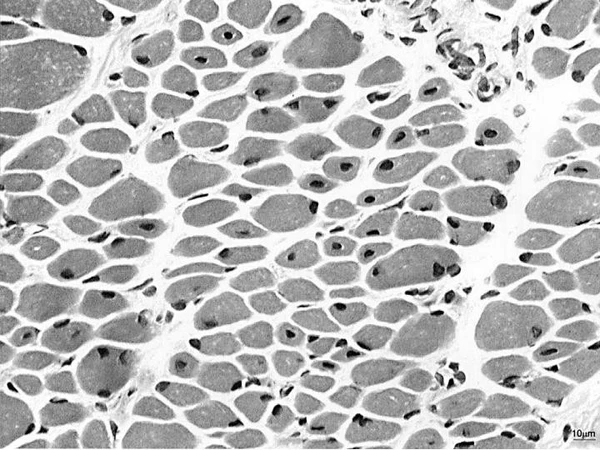

При гистологическом исследовании мышечных биоптатов наиболее частой находкой являются многочисленные внутренние и центрально расположенные ядра. Также обычными признаками служат повышенная вариабельность размеров мышечных волокон и преобладание волокон первого типа, хотя последний признак не наблюдался у женщин-носительниц мутации в гене MTM1. Увеличение доли жировой или соединительной ткани отмечается в части биоптатов, но не было описано у пациентов с BIN1-формой. Скопления ядер (ядерные клампы) регистрировались только у пациентов с DNM2- и BIN1-мутациями, а также у женщин-носительниц MTM1 мутации. Характерным, хотя и не абсолютно специфичным признаком для DNM2-ассоциированной формы является частое наличие радиальных саркоплазматических тяжей, окружающих центральные ядра. Эти структуры лишь изредка встречаются при других формах ЦНМ и у носительниц мутации MTM1. Ядроподобные структуры наблюдались преимущественно у пациентов с мутациями в гене RYR1. Иногда у женщин-носительниц мутации MTM1 могут быть обнаружены так называемые «ожерельные» волокна[7].